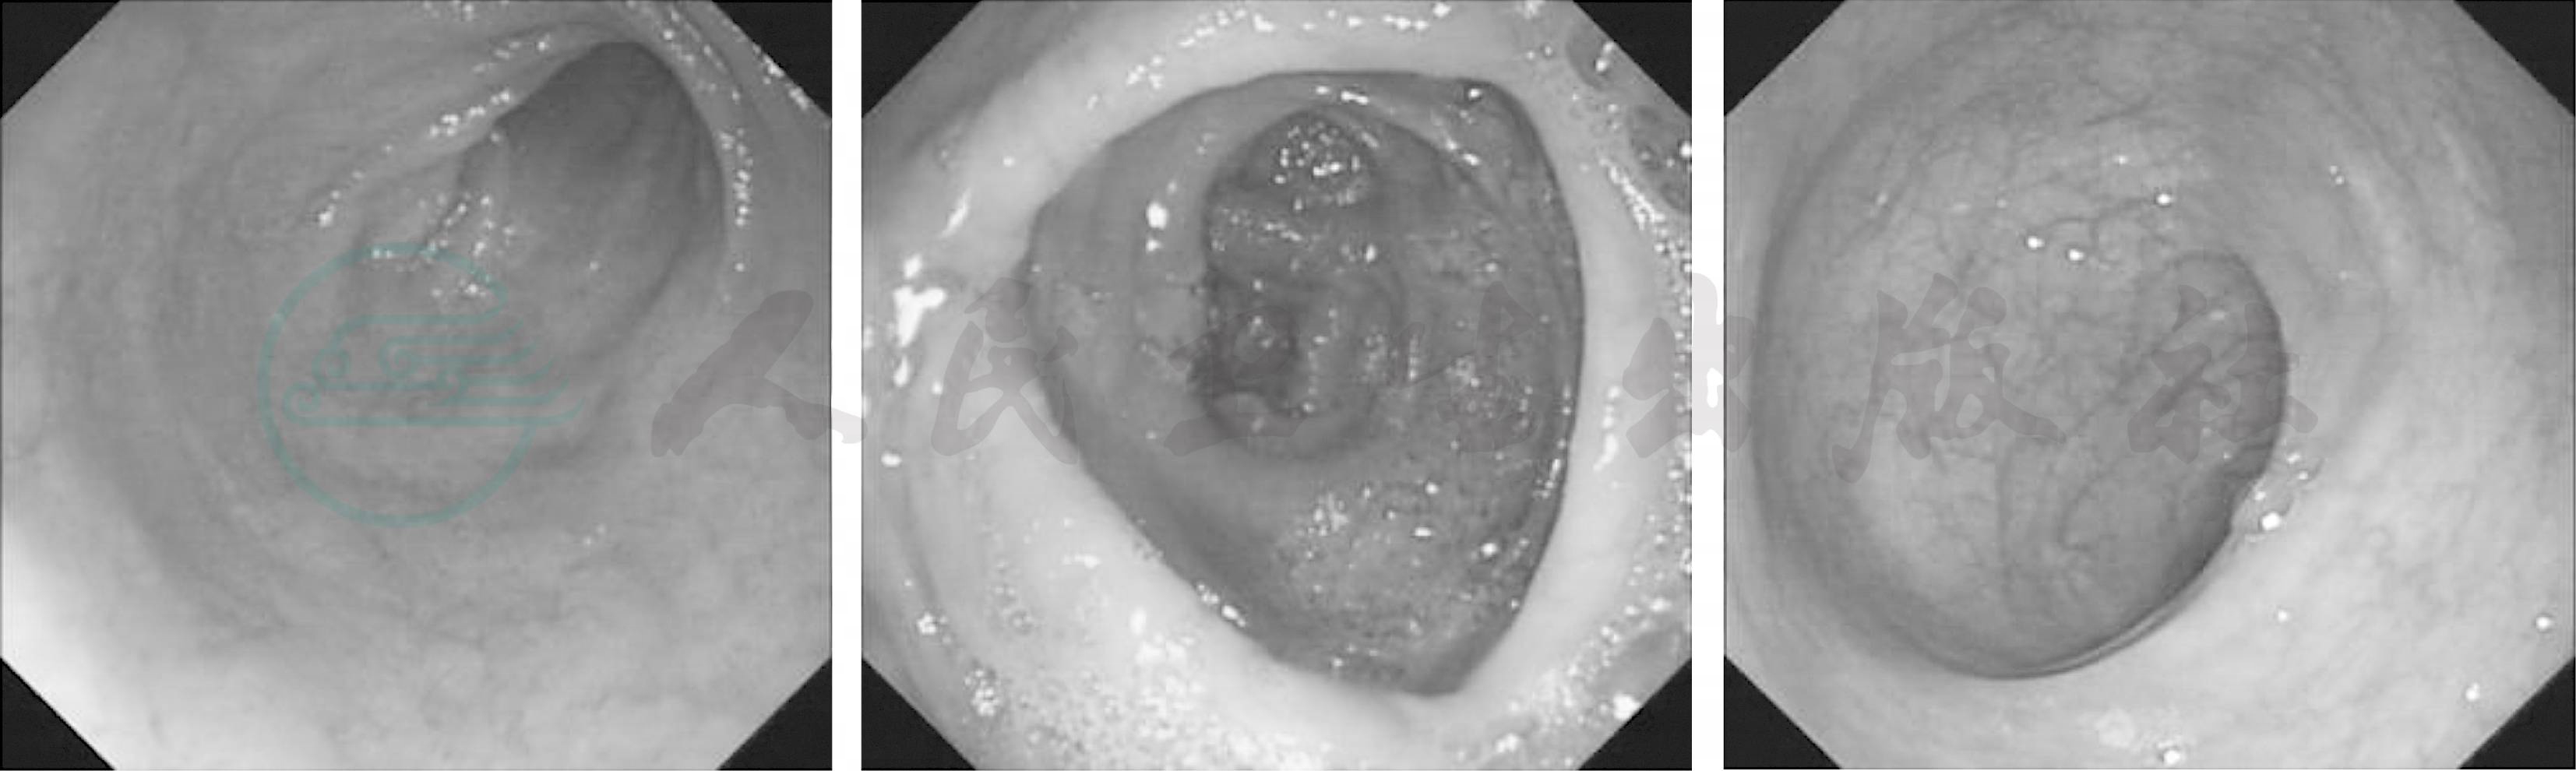

图2 胃镜检查图片

胃体黏膜粗糙颗粒样增生,胃窦黏膜粗糙、充血水肿、点状红斑

辅助检查:血常规:白细胞7.61×109/L、血小板184×109/L、血红蛋白120.6g/L、中性粒细胞百分比61%、嗜酸性粒细胞百分比20%↑、嗜酸性粒细胞1.58×109/L,此后多次复查血常规嗜酸性粒细胞均显著升高(1.47×109/L~1.73×109/L)。大便常规潜血阴性,未见虫卵。小便常规正常。血生化:白蛋白23.7g/L↓;尿酸492μmol/L;转氨酶、胆红素、肾功能、电解质均正常,心肌酶正常。肿瘤指标CA125升高(168U/ml)。大便寄生虫集卵试验阴性、抗体阴性。C反应蛋白(CRP)12.3mg/L,血沉正常,体液免疫指标正常,ANA、dsDNA、ENA、ANCA、抗心磷脂抗体阴性。血FIPL1/PDGFR阴性。腹水常规检查提示白细胞增多,其中嗜酸性粒细胞占10%,病理检查见大量间皮细胞未见嗜酸性粒细胞;腹水人工细胞分类嗜酸性细胞34%。骨髓涂片嗜酸性粒细胞15%,骨髓活检嗜酸性粒细胞轻度增生。腹部CT:①腹腔内恶性肿瘤,并腹腔、盆腔大量积液,腹膜、大网膜、系膜增厚,结节性强化,转移瘤与腹膜间皮瘤鉴别,建议活检(图1);②双肾多发囊肿;③右侧胸腔少量积液。PET-CT:腹膜、大网膜、肠系膜不均匀增厚,右下腹及直肠膀胱陷窝局部腹膜明显增厚,肝门区、腹膜后、肠系膜多发增大淋巴结,以上病灶葡萄糖代谢活性增高,考虑多发转移性病变,原发肿瘤不明确,大量腹水;胃窦部黏膜略增厚,局部葡萄糖代谢稍高,不除外FDG-PET不典型胃癌,建议胃镜检查。随后行胃镜检查:胃体黏膜粗糙颗粒样增生,胃窦黏膜粗糙、充血水肿、点状红斑,活检未见嗜酸性粒细胞(图2)。肠镜检查见回盲部息肉(图3)。